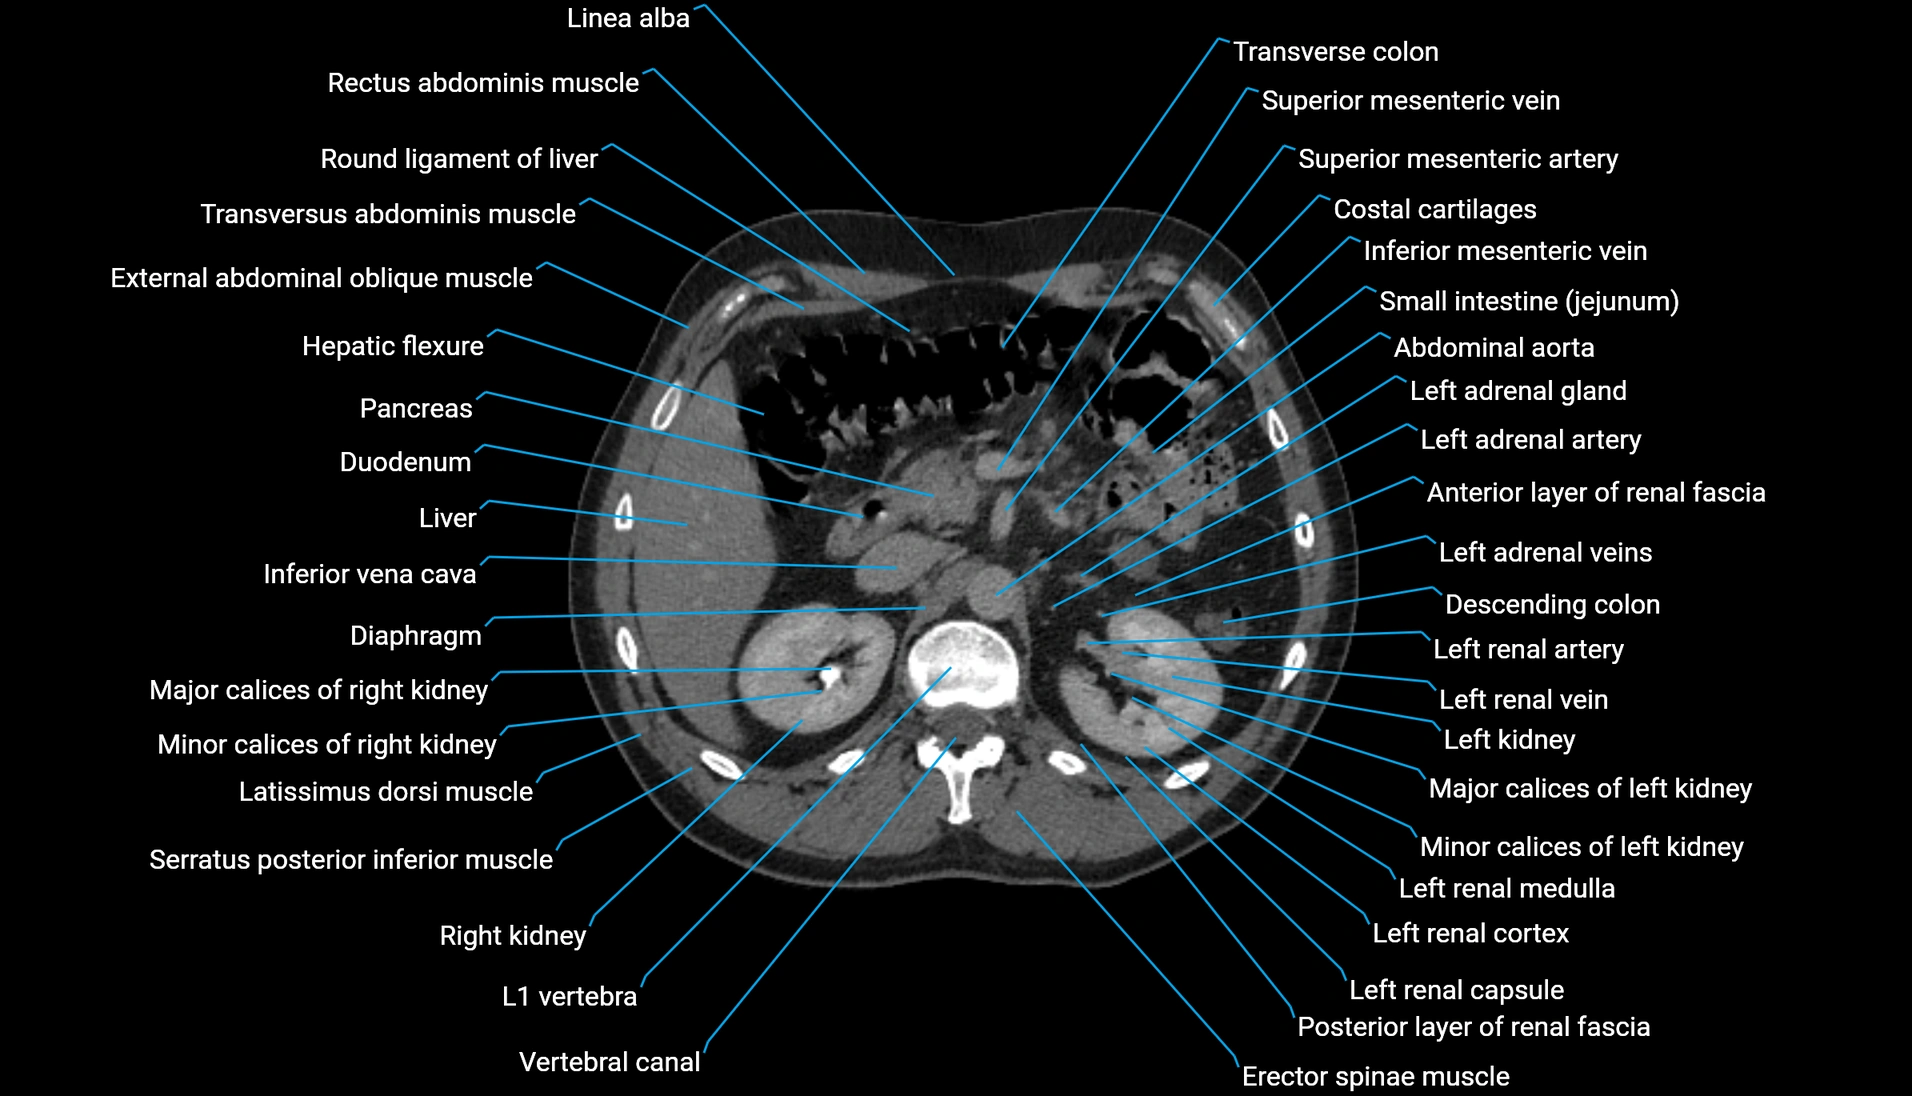

CT Appearance

Non-contrast CT:

-

Demonstrates cortical bone of acetabular rim in excellent detail

Detects fractures, dysplasia, retroversion, or bony overcoverage (pincer impingement)

3D reconstructions used in preoperative hip surgery planning

CT VRT 3D image

CT image